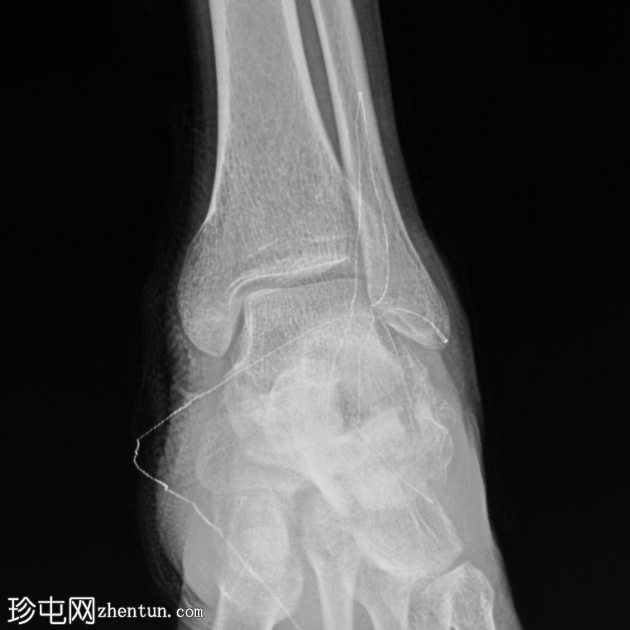

侧位片

关节内粉碎性跟骨骨折(侧位/轴位片)。

未见其他骨折或下胫腓联合损伤。

绷带中的放射性标记物造成伪影。

可以评估Böhler角和Gissane角,尤其是在初始影像检查中关节内骨折延伸不明显的情况下。本例中,Böhler角减小,Gissane角增大。这两个发现均证实了关节内跟骨骨折。